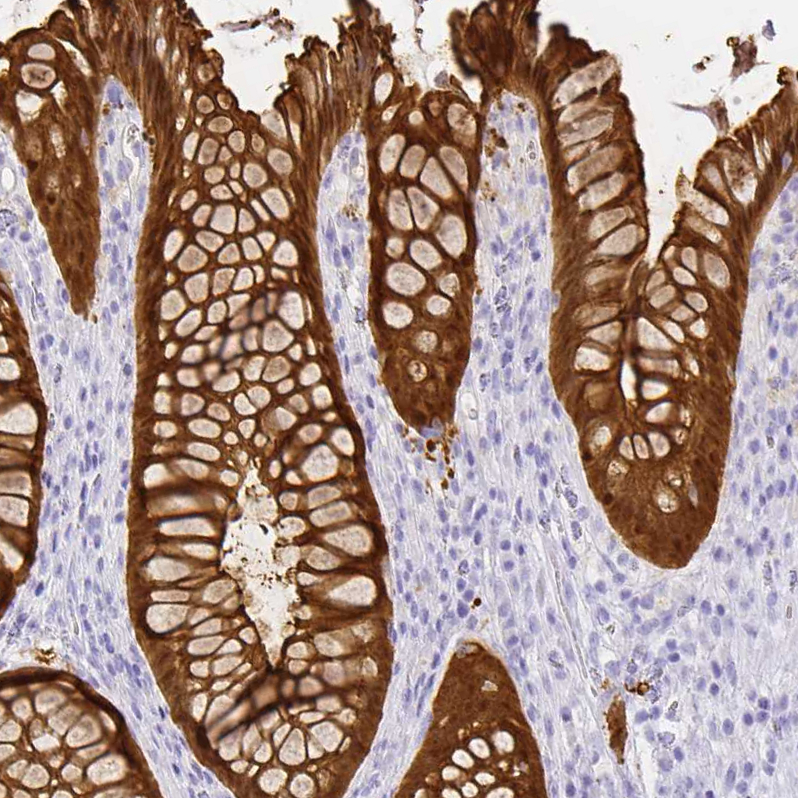

Immunohistochemistry analysis in human colon and cerebral cortex tissues using HPA031186 antibody. Corresponding LGALS4 RNA-seq data are presented for the same tissues.